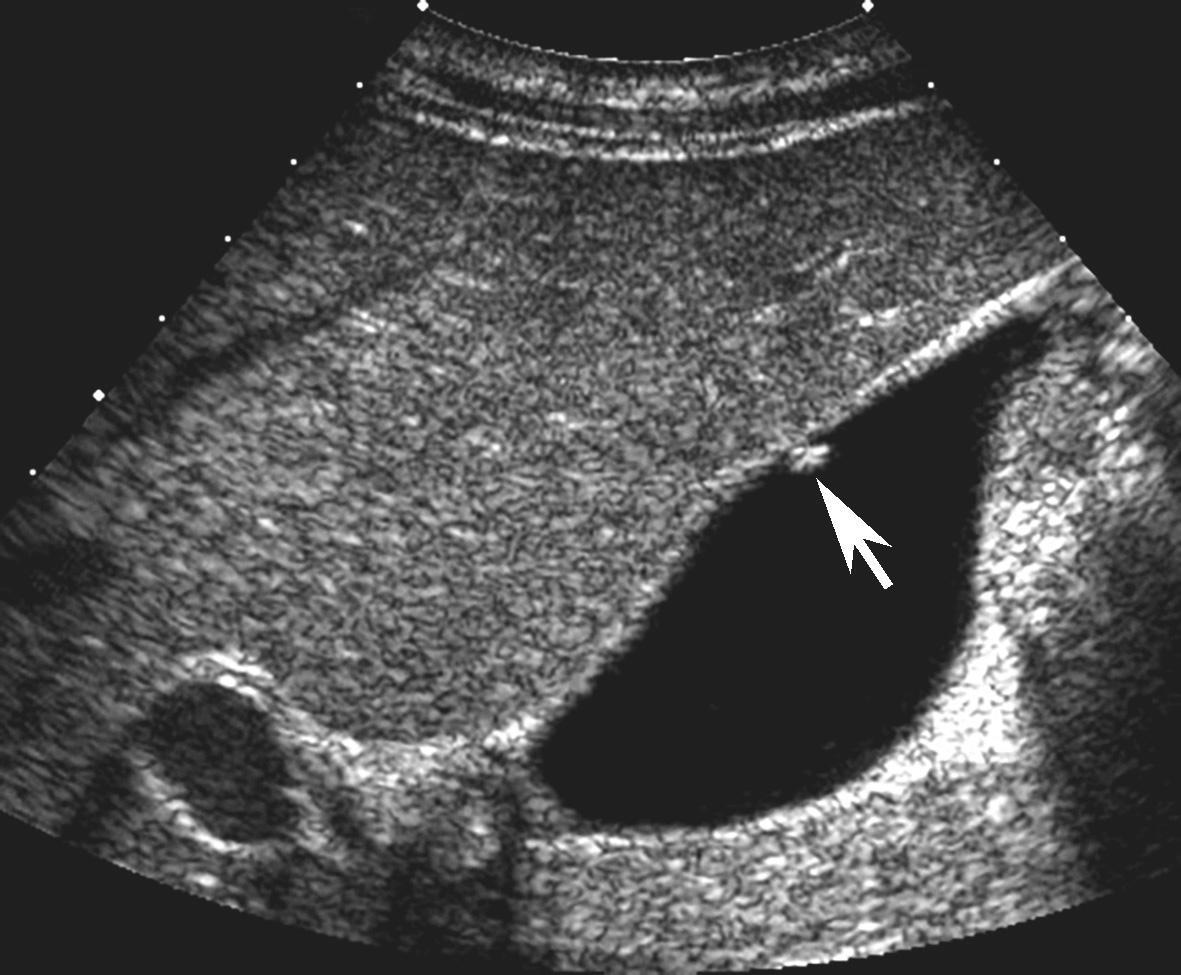

图2-3-1 胆固醇性息肉灰阶超声图像

箭头所示息肉为高回声,形态规则,边界清楚

胆固醇性息肉多呈高回声,较小者可呈强回声伴彗星尾征(图2-3-1);腺瘤性息肉多呈等回声(图2-3-2);炎症性息肉少见,多合并胆囊炎或胆石症。胆囊息肉一般后方无声影,不随体位改变而移动。